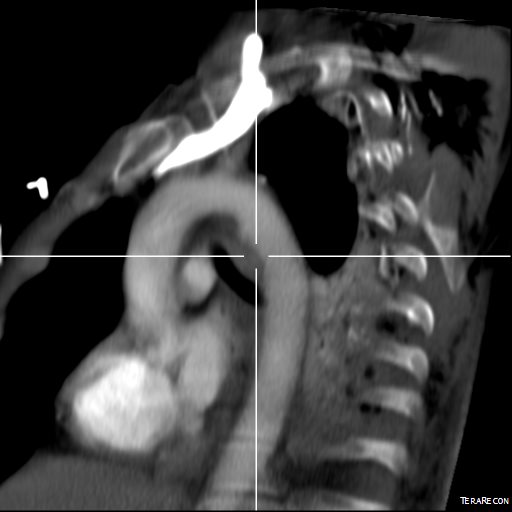

This patient presents with lifestyle limiting claudication and an absent right femoral pulse. ABI is moderately reduced on the right to 0.57, and he had no rest pain. CTA at our clinic revealed an occluded EIA bracketed by severely calcified and nearly occlusive plaque of the common iliac artery (CIA) and common femoral artery (CFA).

The patient was amenable to operation. Traditionally, this would have been treated with some form of bypass -aortofemoral or femorofemoral with a common femoral endarterectomy. While endovascular therapy of the occluded segment is available, one should not expect the patencies to be any better than that of occlusive lesions (CTO’s) in other arteries. Hybrid open/endovascular therapy is an option as well with CFA endarterecotmy and crossing CIA to EIA stents, but I have a better solution.